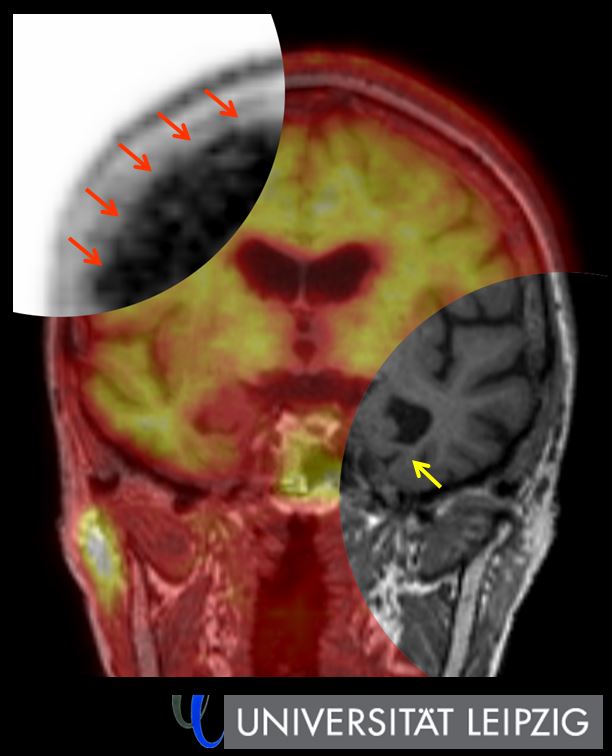

Das am häufigsten für Demenzdiagnostik eingesetzte Verfahren ist die Magnetresonanztomographie (MRT). Mit ihr können Radiologen unter anderem das Volumen bestimmter Hirnregionen, etwa des Hippocampus, ausmessen und auf diese Weise zum Beispiel eine Alzheimer-Demenz erkennen. „Präziser und empfindlicher ist die nuklearmedizinische Demenzdiagnostik mittels PET, denn sie liefert uns bei Demenzpatienten Informationen über molekulare Vorgänge im Gehirn“, so Barthel.

Die klassische PET-Bildgebung, die FDG-PET, macht den Zucker Glukose sichtbar und liefert so Aussagen über den Energieumsatz eines Gewebes. Bei der Demenzdiagnostik hilfreicher ist die seit einiger Zeit intensiv erforschte Amyloid-PET. Sie macht das Amyloid-Eiweiß sichtbar, das sich im Gehirn von Patienten mit Alzheimer-Erkrankung ablagert. „Damit erkennen wir eine Alzheimer-Erkrankung schon Jahre bevor das Hirnvolumen abnimmt“, so Barthel. „Und wir können die Alzheimer-Demenz auch besser von anderen Formen der Demenz abgrenzen.“

Beim 99. Deutschen Röntgenkongress in Leipzig skizziert Barthel die rasanten Fortschritte, die die PET-Bildgebung in der Demenzdiagnostik macht. Insbesondere die Hybrid-Bildgebung aus PET und MRT hält er für ein echtes Zukunftsmodell: „Die kombinierte Bildgebung aus PET und MRT liefert uns bestmögliche Aussagen sowohl zu anatomischen als auch funktionellen Aspekten einer Demenz. Sie ist sehr gut für einen klinischen Routineeinsatz geeignet, weil die Patienten dafür nur einmal kommen müssen und wir alle wichtigen Informationen in einer Untersuchung erhalten.“

Auf Seiten der PET-Komponente ist neben der Amyloid-PET die Tau-PET eine neue Methode, die nach vorn drängt. Sie macht das Tau-Protein sichtbar, das nicht nur bei der Alzheimer-Erkrankung auftritt, sondern auch bei einigen anderen neurodegenerativen Erkrankungen. Das Tau-Protein korreliert eng mit dem Krankheitsverlauf und erlaubt deswegen recht präzise Aussagen zum Stadium einer neurodegenerativen Demenz.